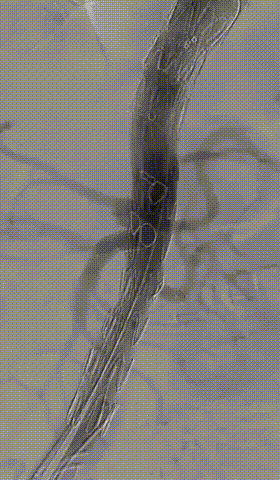

患者男性,63岁,急性胸痛5小时入院。该患者从主动脉弓部直到髂动脉撕裂的 B型夹层,为全程三阶段管理的病例。第一阶段进行降主动脉几乎全程覆盖。在第二阶段真腔狭小,下肢有缺血的表现,行3D打印模型下的F/B EVAR手术。第三阶段在做完主髂段后再做主髂,尽量保髂内动脉重建。采用激光原位技术将双侧髂内动脉全部保留,减少髂内动脉对脊髓缺血的影响。手术中发现出现假腔II型内漏,内漏相对较小可以随访观察。最近随访观察肠系膜下动脉内漏完全消失。

第三次治疗(2021.10.28)